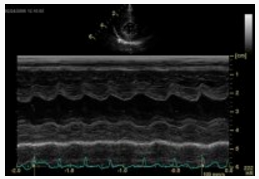

Mediante la valutazione in M-mode del ventricolo sinistro si effettuano le misurazioni degli spessori parietali al termine della diastole e si classifica HCM felina come:

Normale: fino a 5,5 mm

Borderline: 5,5-6 mm

Lieve: 6-6,5 mm

Moderata: 6,5-7 mm

Severa: >7mm